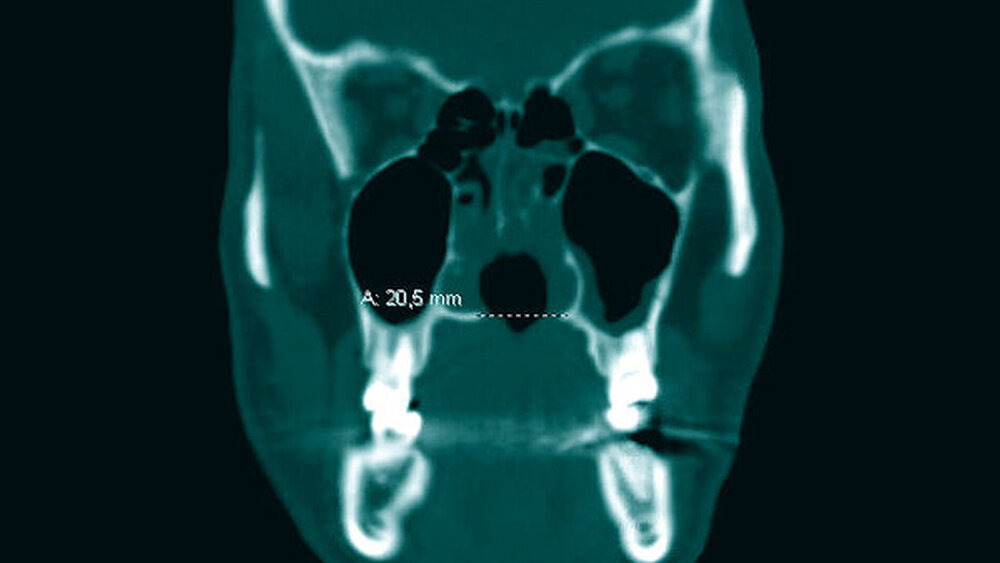

Es folgten eine Blutabnahme mit Routinelabor und Serologie (Lues, HIV, Hepatitis C) sowie eine Alginatabformung zur Herstellung einer Tiefziehschiene. Der Patient wurde zur weiteren Planung und Schieneneingliederung am Folgetag einbestellt. Nach einer raschen CT-Untersuchung mit Kontrastmittel Kopf/Hals (Abbildungen 1 bis 3) erfolgte eine endoskopische Rhinoskopie mit bioptischer Sicherung in ITN unter stationären Bedingungen.

CT-Befund Kopf/Hals: Weichteil-dichte Raumforderung im Bereich der linksseitigen Ethmoidalzellen, vollständige Verlegung des Sinus frontalis links sowie teilweise Verlegung rechtsseitig; zirkuläre Schleimhautschwellung in beiden Sinus maxillaris bei ausgedehnter Destruktion von Nasenseptum, Nasenmuscheln, der medialen Sinuswände und des Hartgaumens sowie subtotal verlegte linke Mastoidzellen bei regelrechter Belüftung vom Mittelohr beiderseits.